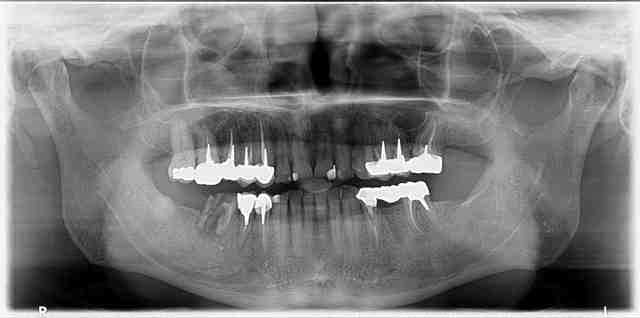

Quelques pano réalisées avec Kodak 9000 3D que j'ai en stock

Edit : je sais pas pourquoi elles sont pixelisées à mort sur Nonol...

P18 dbjrrr - Eugenol

Oui j'ai eu des images comme la 0123 (la première radio). Les autres sont très pixellisées en effet.

Merci pour tes images. Je trouve la qualité pas mal du tout.

merci pour les images, mais moi je trouve la qualité très médiocre